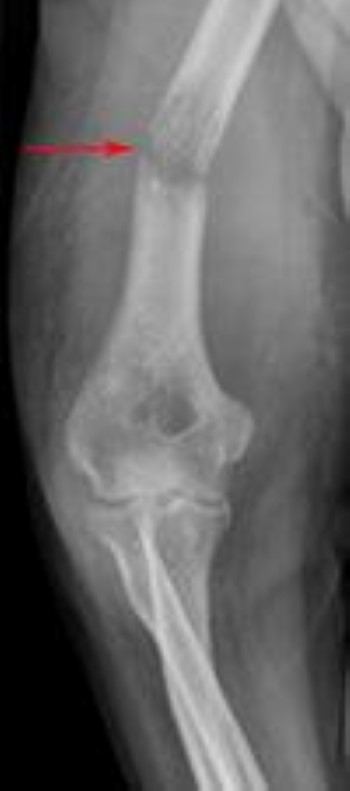

Pathologic fracture

This X-ray of the upper arm shows a pathological fracture in the humerus (arrow).